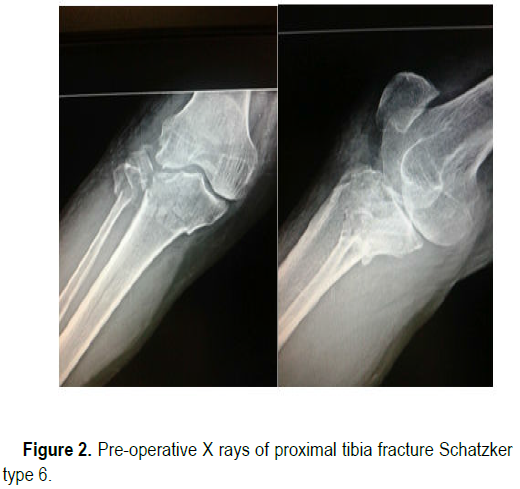

Active assisted range of motion was started at three weeks and full range of motion was obtained by six weeks. The patients were followed up at six weeks, three months, six months and one year post operatively (Figure 2-5).

clinical-research-fracture

Figure 2. Pre-operative X rays of proximal tibia fracture Schatzker type 6.